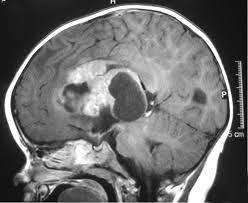

What Causes Brain Cancer In A Child - Treatment For Kids Brain Tumors Can Cause Hearing Problems Cancer Today / And they vary between children.. This is different to cancers that have spread to the brain from somewhere else in the body. Brain tumors are the most common solid tumors affecting children and adolescents, with close to 5,000 children diagnosed each year.; Up to 10% of all cancers in children are caused by a heritable (germline) mutation (a mutation that can be passed from parents to their children). And they vary between children. Morning headaches or headaches that go away after vomiting;

Up to 10% of all cancers in children are caused by a heritable (germline) mutation (a mutation that can be passed from parents to their children). The majority of brain tumors have abnormalities of genes involved in cell cycle control, causing uncontrolled cell growth. There are many types of brain tumors and the treatment and outlook for each is different. Most cancers in children, like those in adults, are thought to develop as a result of mutations in genes that lead to uncontrolled cell growth and eventually cancer. See your gp if your child has any symptoms of a brain tumour to get them checked over.

Brain Cancer Anatomy Biology Brain Cancer Children Common En Health Human Nausea Glogster Edu Interactive Multimedia Posters from c3f827.medialib.edu.glogster.com Though uncommon, a family history of brain tumors or a family history of genetic syndromes may increase the risk of brain tumors in some children. Brain tumors and other nervous system tumors make up about 27 percent of childhood cancers. Brain tumour symptoms can be very similar to those of childhood illnesses. Unusual sleepiness or change in activity level; This leads to swelling and increased pressure inside the skull. The tumor grows and presses against the pons, causing problems with body functions controlled by this part of the. Some kids who have certain genetic conditions have a greater chance of developing brain tumors. The cause of most childhood brain and spinal cord tumors is unknown.

Brain and spinal cord tumors in children are the result of cells growing out of control.

This leads to swelling and increased pressure inside the skull. Signs and symptoms of brain tumors are not the same in every child, but may include : Brain tumors are the most common solid tumors affecting children and adolescents, with close to 5,000 children diagnosed each year.; Remember the symptoms we list here are not usually cancer. There are many kinds of brain tumors. Brain tumors, either malignant or benign, are tumors that originate in the cells of the brain. Alan cohen, m.d., director of pediatric neurosurgery at johns hopkins children's center, shares the most common signs and symptoms that could point to a potential brain tumor. Brain tumour symptoms can be very similar to those of childhood illnesses. Children with certain genetic conditions have an increased risk for tumors of the central nervous system. What you need to know. What are the types of brain tumors? Most cancers in children, like those in adults, are thought to develop as a result of mutations in genes that lead to uncontrolled cell growth and eventually cancer. The majority of brain tumors have abnormalities of genes involved in cell cycle control, causing uncontrolled cell growth.

Doctors classify brain and central nervous system tumors based on where they form and the kind of cells they involve.

Tumors can occur at any age. The tumor may start in your child's brain or travel to his brain from another body area. Many children with a brain tumor experience headaches before their diagnosis. Brain tumors, either malignant or benign, are tumors that originate in the cells of the brain. What are the types of brain tumors? Signs and symptoms of brain tumors are not the same in every child, but may include : Most cancers in children, like those in adults, are thought to develop as a result of mutations in genes that lead to uncontrolled cell growth and eventually cancer. Although the drugs can be taken orally in pill form, in children with pediatric brain tumors the drugs are usually injected into a vein (intravenous chemotherapy). Vision, hearing, and speech problems; The cause of most childhood brain and spinal cord tumors is unknown. Brain and spinal cord tumors in children are the result of cells growing out of control. Most often, it's not known why children without inherited syndromes develop brain or spinal cord tumors. Brain tumors can cause pressure on the brain, causing the following symptoms: